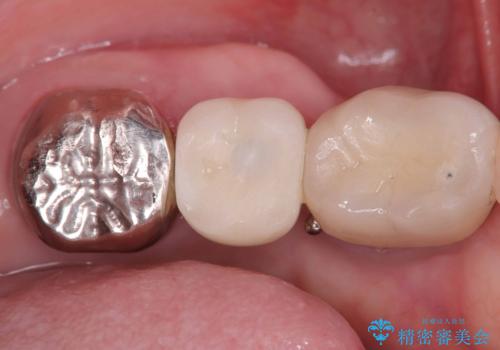

【1Dayインプラント治療! 低侵襲で短期間での治療】 咬むと歯が痛い! 歯根破折